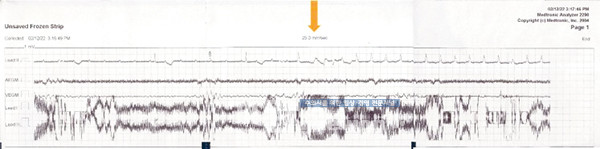

Pacemaker의 리드를 우심실벽에 고정 후 ECG와 근전도를 실시하였습니다. 근 전도상 P로 표시된 pacing은 있으나 뒤따라오는 QRS가 없는 것을 알 수 있습니다.

수술 중 심실 벽에 pacemake를 연결 후 pacing에 대해서 QRS 반응이 보이고 있습니다.

수술 후 EGM 상에서 P파 이후에 탈분극이 일어나는 모습을 확인할 수 있습니다.